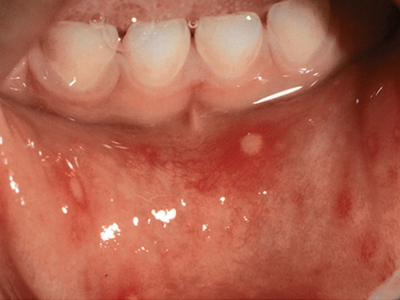

口腔

水疱

手足口病严重水疱图片

手足口病严重时造成整个嘴唇内侧布满密密麻麻的小水疱,疱液混浊,疱壁较薄亮,独立存在,多为圆形或类圆形。水疱周围绕有红晕,整个嘴唇内侧红肿。部分水疱由于前牙的摩擦而发生破溃,形成小的溃疡。由于疼痛明显,患儿可有流口水、拒食、哭闹的情况。